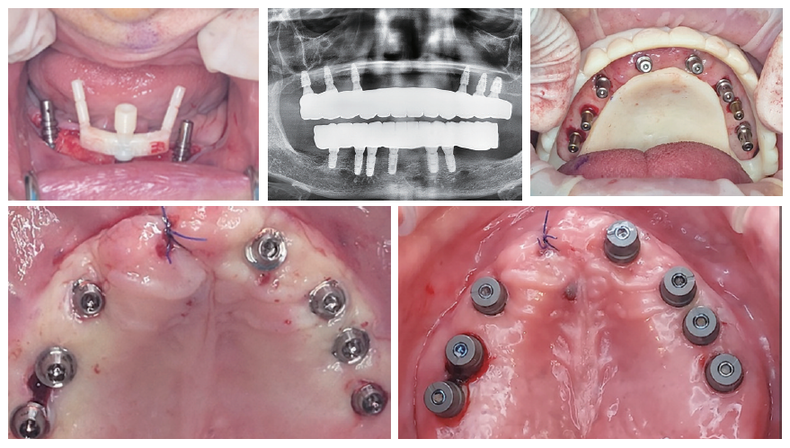

All-on-X 치료는 각도 식립, 즉시로딩, 그리고 보철의 정확성이 동시에 요구되는 술식이다. 이를 고려했을 때, 유지·관리와 Retribility가 뛰어난 cementless 보철 시스템은 선택이 아닌 필수라고 판단했다. 여러 시스템을 임상에 적용해 본 결과, FOXDEN 시스템은 국내 임상 환경에 사장 현실적인 대안이 될 수 있다고 느꼈다.

기존 MUA를 이용한 All-on-X 술식은 수술 후 Fixture 각도에 따라 Abutment와 Cuff를 개별적으로 선택해야 하며, 수술 후 보철 과정 또한 복잡하다. 임시 보철 제작 시 MUA 실린더 리라이닝 방식은 Chair time이 길고, 술자 의존도가 높다는 한계가 있었다.

또한 구조적으로 MUA는 픽스처에 연결되는 연결체의 역할에 집중돼 있어, 보철물은 스크루에만 의존해 교합력을 지지하게 된다. 이는 장기 사용 시 스크루 풀림이나 보철 안정성 측면에서 아쉬움이 남았다.

수술 후 Cuff를 선택해 Abutment를 연결하고 스캔바디 체결만으로 바로 디지털 인상이 가능하다. 즉시 디자인 후 3D 프린팅을 통해 임시 보철 제작이 가능해, 전악 수술 후 3시간 이내 즉시 로딩이 가능해졌다.